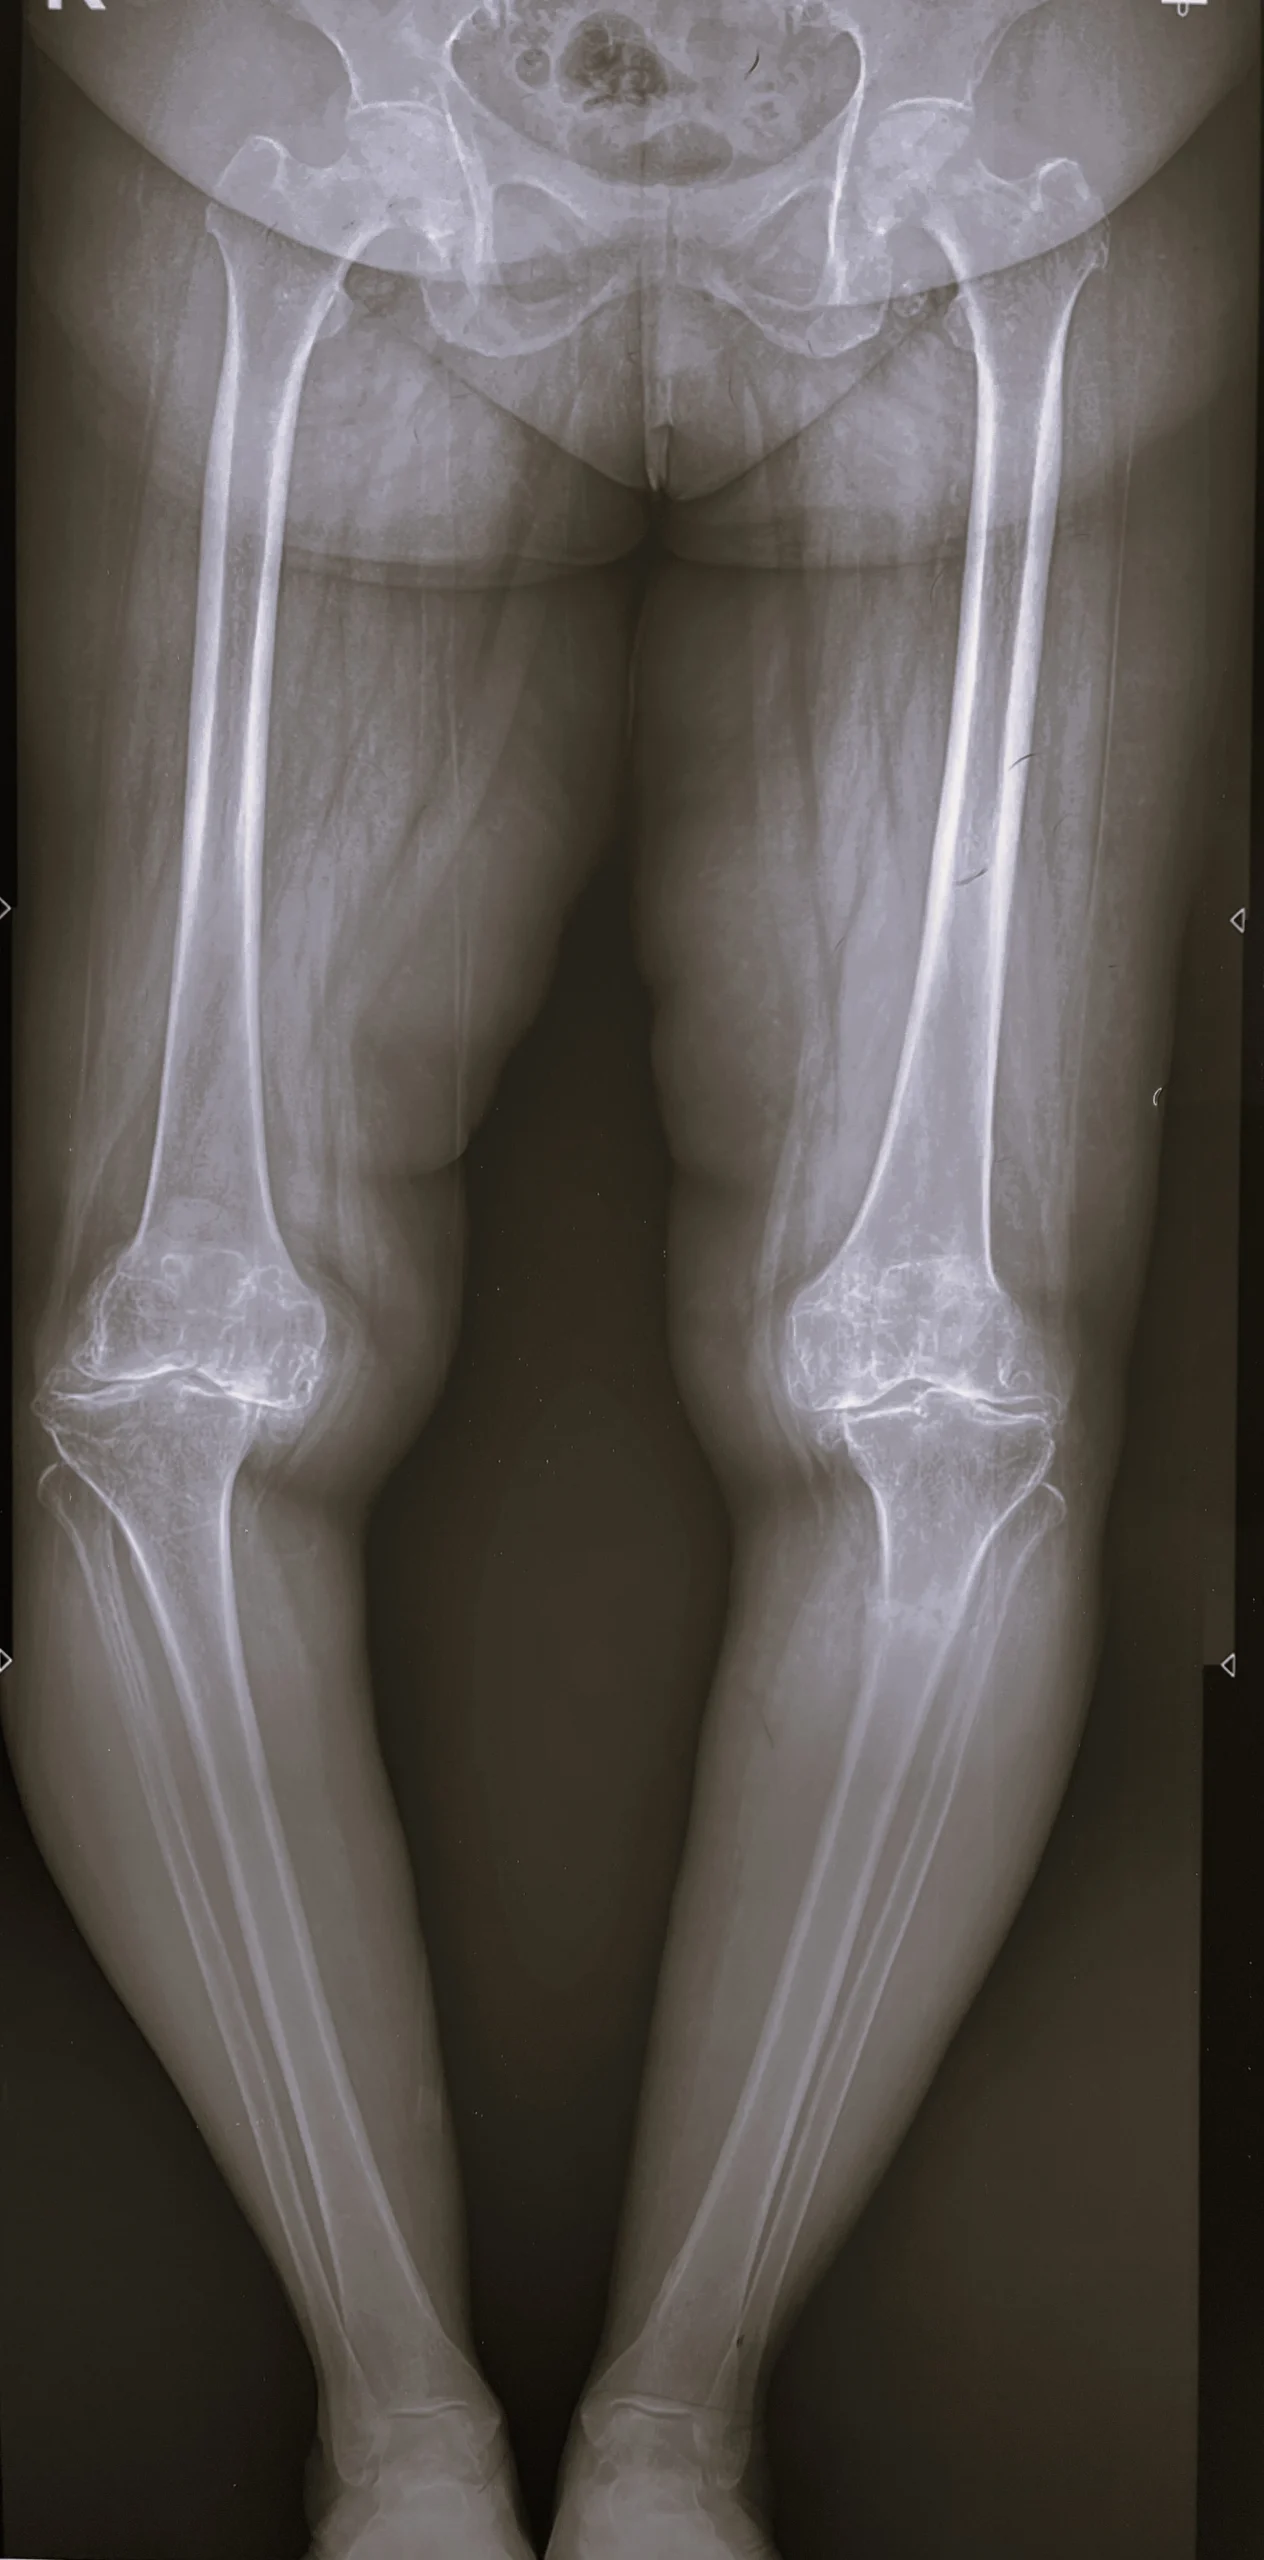

Stress Fracture of Tibia with Rigid Varus Deformity

Pre-Op Scanogram